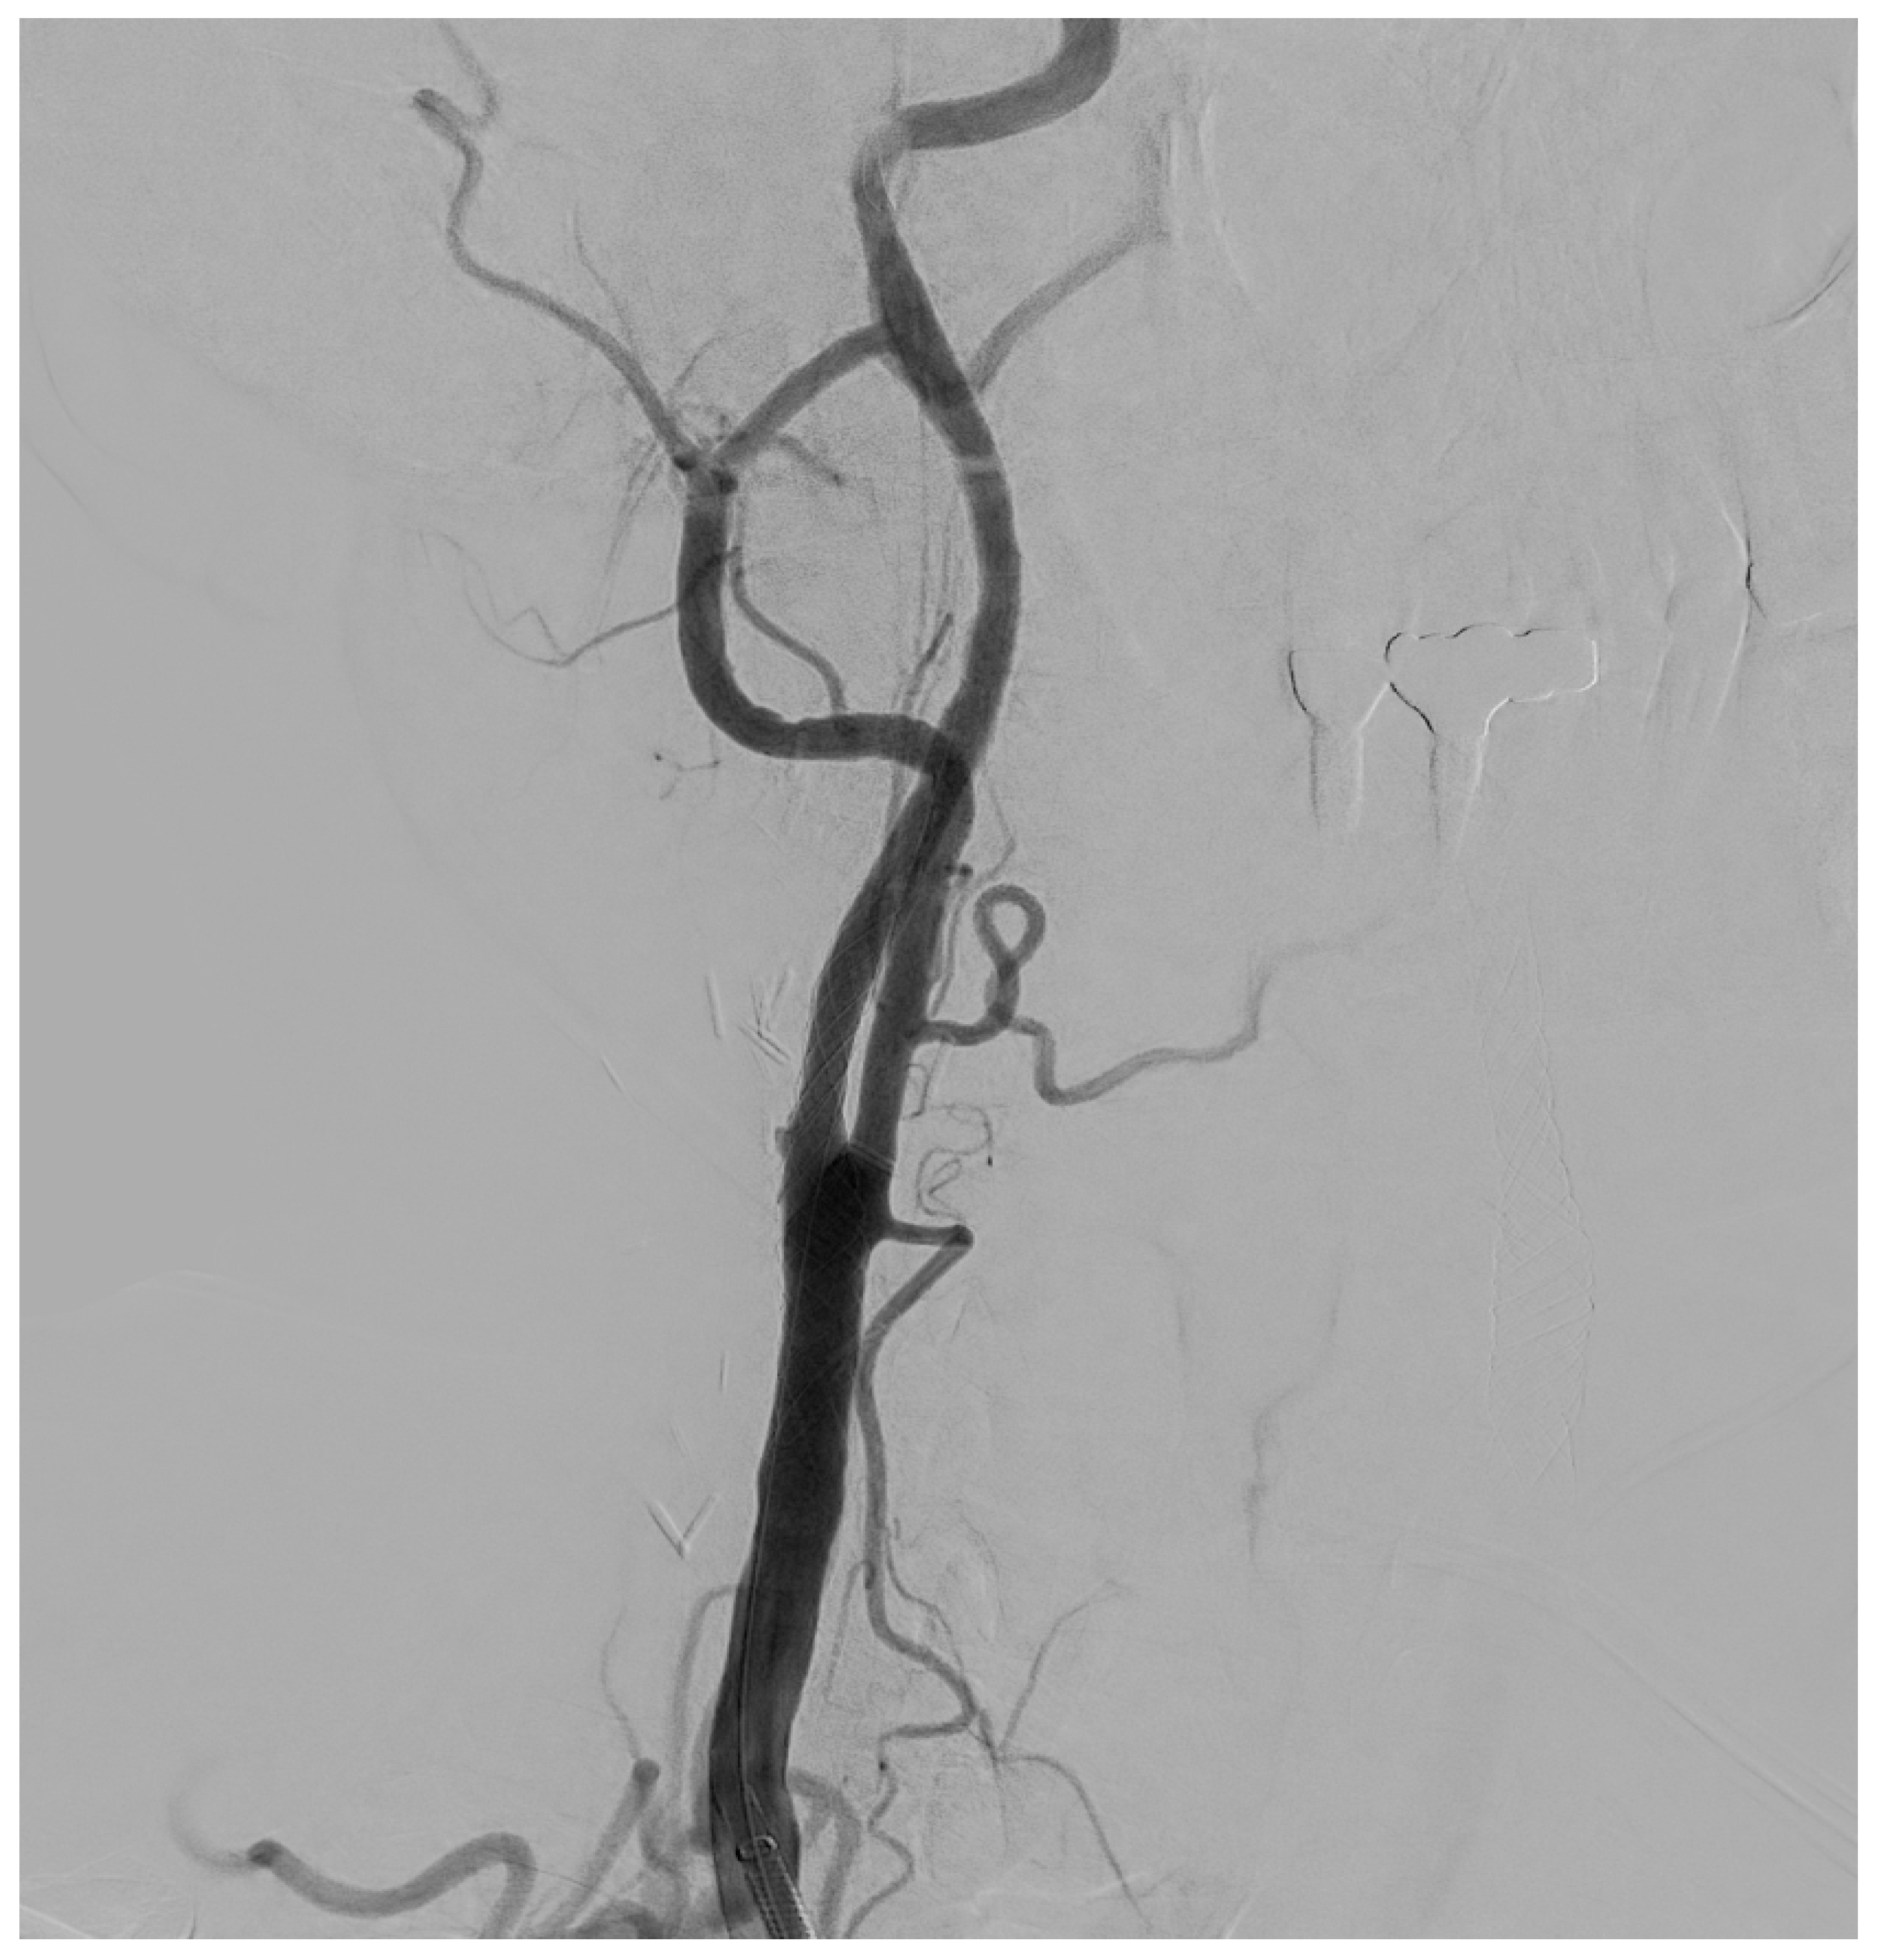

Figure 5. Final DSA control, in a patient with significant (>50%) stenosis of the ICA who has been treated by positioning a closed-cell stent (Boston Scientific Wallstent, 8 × 30 mm, 300 Boston Scientific Way Marlborough, MA 01752-1234) dilated with a balloon catheter (Ultraverse PTA dilatation catheter 6 × 20 mm, Becton, Dickinson and Company’s, 1 Becton Drive, Franklin Lakes, New Jersey 07417, USA).

The procedure is performed in the angiographic suite, under mild sedation to monitor the neurological status of the patient, by arterial vascular access, usually femoral. With the wire–catheter system, the common carotid artery (CCA) of the pathological side is selectively catheterized and a diagnostic angiography is performed to identify the stenosed area (Figure 3). The stenosis carotid tract is crossed through the wire–catheter system, and only after the placement of a neuroprotection device in the ICA, a balloon angioplasty is performed to compress the atheromatic lesion and restore the original luminal vessel diameter. Regarding neuroprotection, today we have two classes of embolic protection devices available: a coaxial umbrella-like filter positioned in the distal ICA (Figure 4) or hemodynamic balloon block systems with reversal flow that can be placed either proximally or distally to the carotid stenosis with overlapping results in reducing the distal embolic phenomena risk but with a higher rate of periprocedural vasospasm in the case of a distal umbrella-like filter [53]. At this point, it is necessary to inject 1 mg of atropine to avoid vasospasm before releasing a permanent endovascular stent. We have three types of endovascular stents such as open-cell, closed-cell, or double-layer (Figure 5). Open-cell stents were worse than closed-cell due to the higher degree of plaque protrusion and the procoagulant state induced by the stent that can trigger embolic phenomena, recording a higher rate of stroke or restenosis at 30 days. The double-layer stents are still in the process of approval by the FDA although they have shown in some clinical trials strongly encouraging results with a risk of adverse events at 30 days <2% [54].